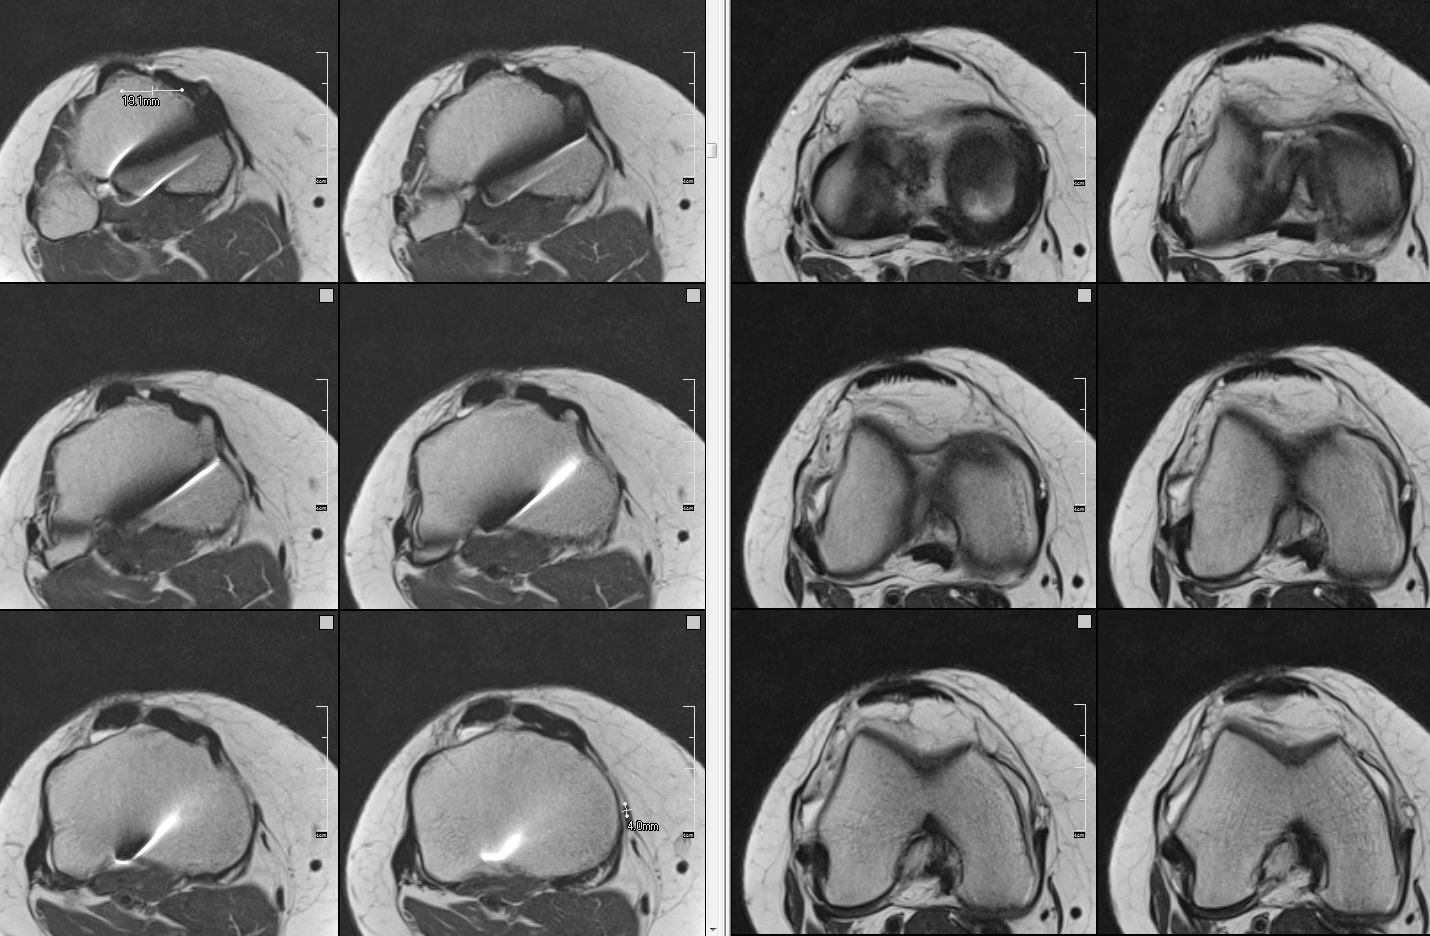

Figure 2 for case Soft tissue patellar-lowering procedure

Figure 2